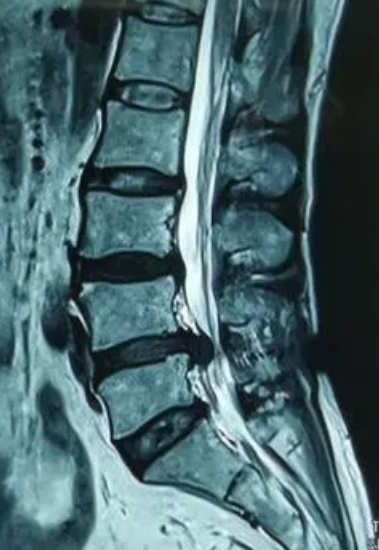

这下彻底慌了,赶紧给我学医的同学打电话。在他的建议下我转到本地一家知名骨科医院。这里的医生给我开了 MRI (磁共振成像)的单子,并且专门打了电话,安排加急处理。

MRI 即磁共振,对于肌肉、韧带等软组织的成像要比 CT 的效果好。通过MRI ,医生发现我的椎环断裂,脊髓液都流了出来。

再晚来一会儿,我就会瘫痪!

就好像我这样,椎环已经断了,脊髓液哗哗地往外流,这种情况下必须手术,贴膏药、烤电、物理牵引什么的根本起不到正向作用,甚至有可能会让病情更加严重。

作者将自己的致伤因素、治疗过程、手术选择,以及术后的恢复和特殊感觉都比较清楚地讲述了出来。腰椎间盘突出是一种常见的脊柱疾病,通常由于椎间盘的纤维环破裂,髓核突出压迫神经根或脊髓引起。